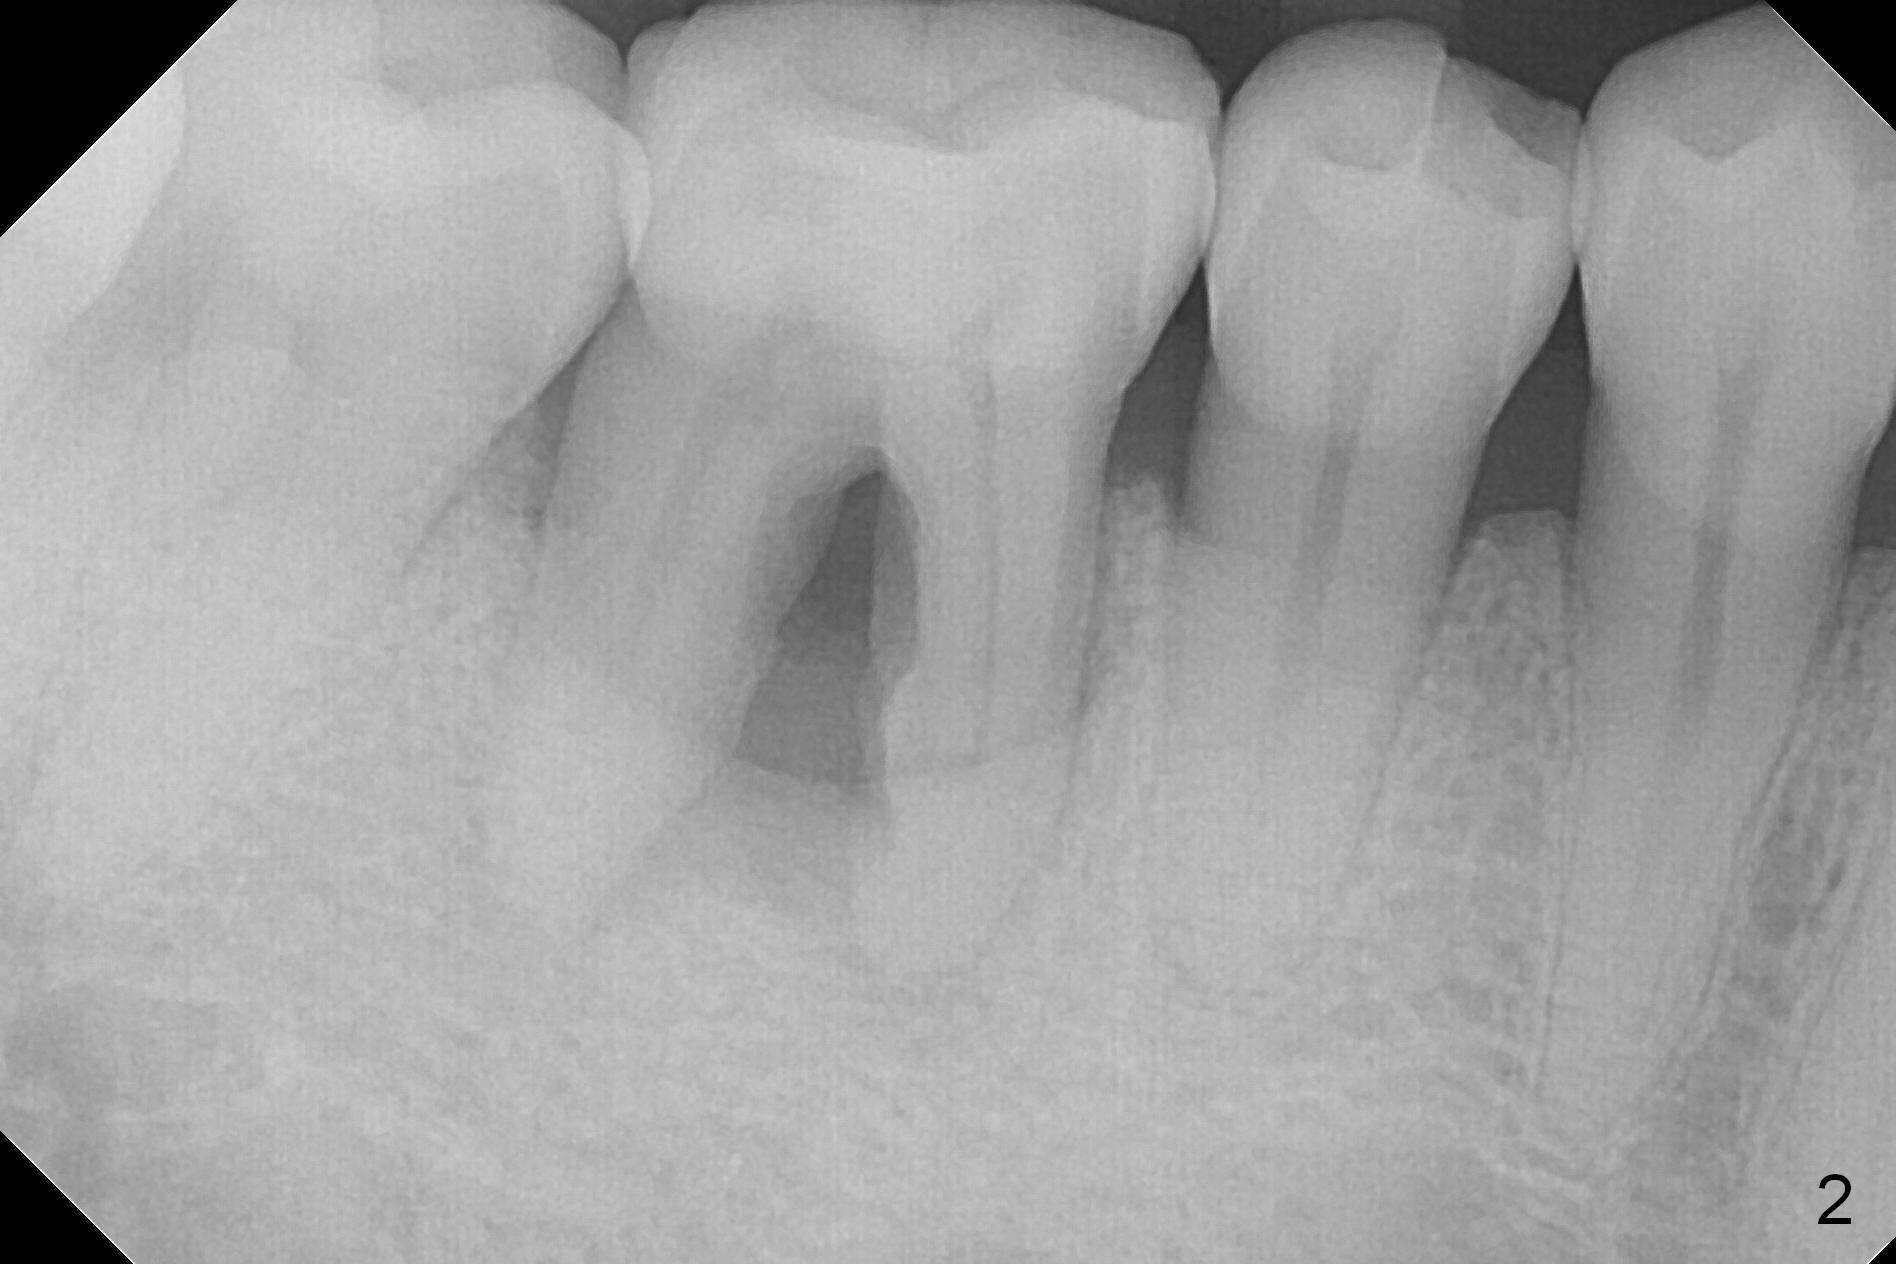

A 45-year-old man had Class I or II furcation involvement at the tooth #30 ten years ago (Fig.1, Classifications of Furcation Involvement - Stedman's Online). He returns recently requesting composite to seal Class IV furcation involvement (Fig.2). It appears that the tooth is unsalvageable (Fig.3 (no Antibiotic)). Since it is difficult to differentiate the upper (yellow dashed line) vs. the lower (brown line) borders of the Inferior Alveolar Canal, the initial depth will be 8 mm. Take panoramic X-ray if necessary. Because of severe bone loss, an abutment with 6 mm cuff is to be used (Pink area).